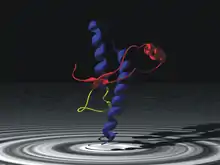

The infectious agent is a misfolded form of a host-encoded protein called prion (PrP). Prion proteins are encoded by the Prion Protein Gene (PRNP).[21] The two forms of prion are designated as PrPc, which is a normally folded protein, and PrPsc, a misfolded form which gives rise to the disease. The two forms do not differ in their amino acid sequence; however, the pathogenic PrPsc isoform differs from the normal PrPc form in its secondary and tertiary structure. The PrPsc isoform is more enriched in beta sheets, while the normal PrPc form is enriched in alpha helices.[19] The differences in conformation allow PrPsc to aggregate and be extremely resistant to protein degradation by enzymes or by other chemical and physical means. The normal form, on the other hand, is susceptible to complete proteolysis and soluble in non-denaturing detergents.[14]

It has been suggested that pre-existing or acquired PrPsc can promote the conversion of PrPc into PrPsc, which goes on to convert other PrPc. This initiates a chain reaction that allows for its rapid propagation, resulting in the pathogenesis of prion diseases.[14]